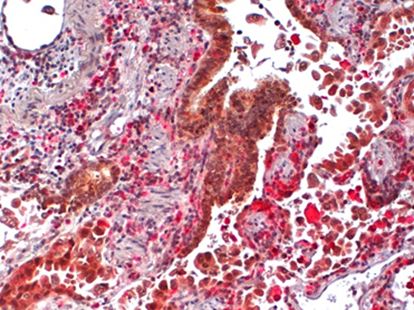

Multiplex IHC Staining: Human Lung CD68/cb-1 Single IHC Staining: Human Placenta, CD34

CD34 Kidney 40x